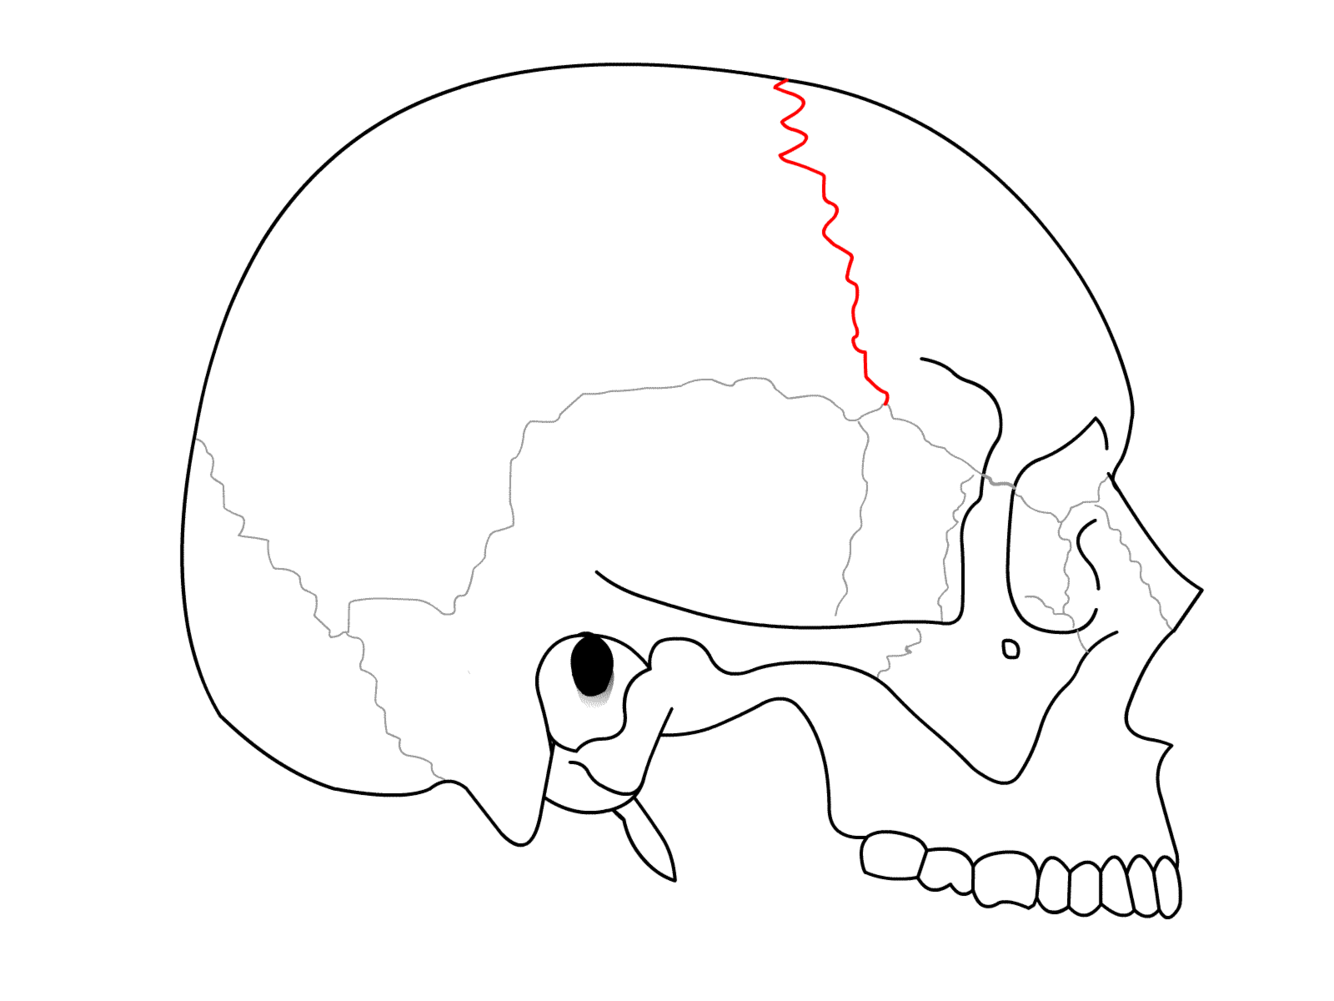

What are the sutures of the skull and what are the joining points you need to know?

What suture is this?

Coronal suture